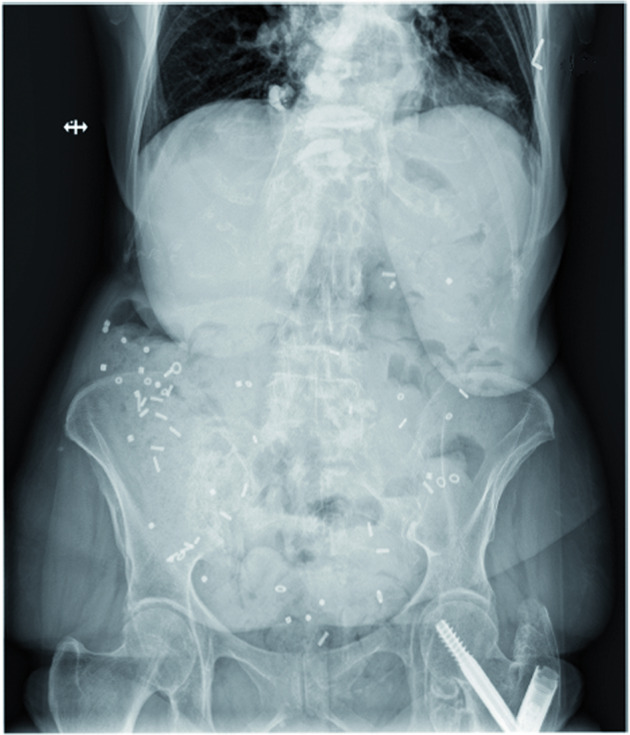

Revisamos el conocimiento actual sobre la fisiopatología, la fisiopatología, el diagnóstico y el tratamiento del tracto gastrointestinal en la enfermedad de Parkinson y brindamos recomendaciones para el manejo en la práctica diaria. npj Parkinson's Disease, 22 de marzo de 2022